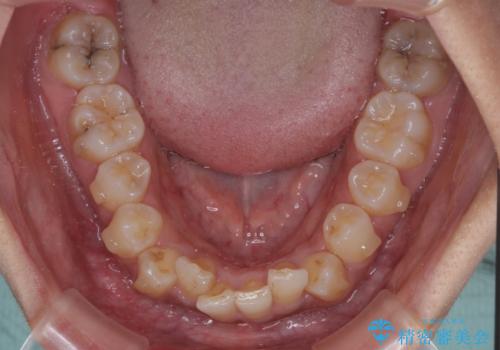

前歯のデコボコと隠れてしまう下顎前歯 インビザラインですっきりと改善

- 前歯のデコボコと、深い咬み合わせにより前歯が隠れていることを気にして来院された患者様です。

海外に長期滞在する予定があるとのことで、インビザラインにて矯正治療を行うこととしました。